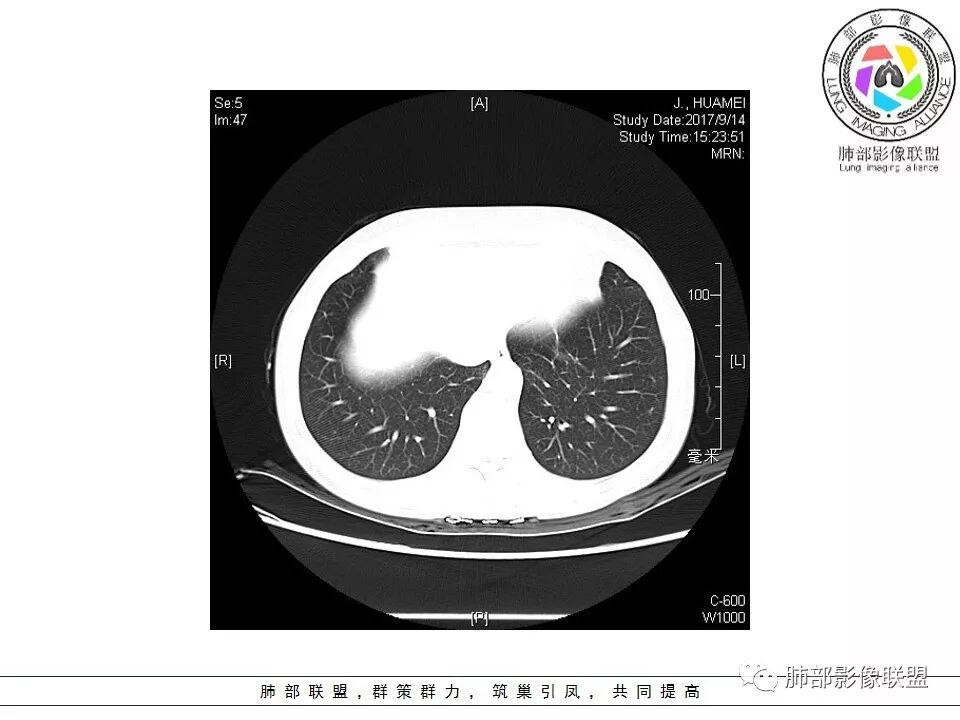

这个病灶边缘还是有一点点恶性征象,有分叶,似乎有点地方还有一些小毛刺样感觉

部分区域整体以膨隆为主,部分区域稍收缩

内部支气管走形非常自然,达远端稍扩张;内部血管穿行也非常自然

内部密度比较均匀,我们一般来说,首先良性肿瘤不支持,因为它里面的血管走形太自然了;然后就是炎性病变跟恶性肿瘤,但是它的边缘膨隆比较厉害,有些地方还毛刺,不是很清楚,倾向一个恶性病变

恶性的血管穿行自然,包括支气管稍扩张,最常见还是淋巴瘤,它强化比较均匀;

粘液腺癌一般支气管扩张比较罕见,这个密度及强化太均匀,不是很符合,所以把淋巴瘤放前面,癌待排;

方向定在恶性的,炎性病变不是很符合

病灶分布:因为肺内淋巴瘤主要侵犯对象是肺间质和支气管黏膜下组织,病灶主要位于在沿支气管血管束分布、肺间质及胸膜下,病灶可跨叶分布

病灶的密度:密度均匀,部分病灶内可见空洞及气液平,轻中度均匀强化

病灶的边缘:有膨隆,浅分叶,也有平直、收缩,平直收缩是因为肿瘤组织浸润致肺泡塌陷及周围纤维组织增生,牵拉正常的肺组织向病灶中心形成聚拢状改变,似呈“炎性”改变。

支气管充气征伴或不伴支气管扩张:肿瘤细胞沿肺间质及支气管黏膜下组织浸润,支气管管壁未见明显破坏,管腔内未见肿瘤细胞充填,呈现充气支气管征;充气支气管走行自然,无扭曲、僵硬,内壁管腔光滑,支气管管壁见增厚并常有管腔的扩张,含气支气管可呈串珠样不均匀扩张,扩张明显处呈空腔样或皂泡样的囊状含气影;支气管扩张目前有两种意见:一是由于肿瘤组织起源于肺间质,肿瘤沿或跨越脏器解剖结构生长,原有解剖结构残留,周围增生的纤维结缔组织牵拉导致支气管扩张;二肿瘤侵犯支气管粘膜下植物神经丛致平滑肌张力丧失;而这类支气管扩张在肿瘤治疗后有时可消失。

血管造影征:肿瘤组织浸润引起间质增厚、肺泡壁破坏、肺泡腔充填,而周围充盈血管走行自然,未受肿瘤侵犯。

间质性改变:多位于病灶周围,可见边缘磨玻璃密度影或晕征及树芽征象,周围组织间质增厚并且有结节感,病理基础为肿瘤细胞浸润细支气管周围间质及肺泡壁。